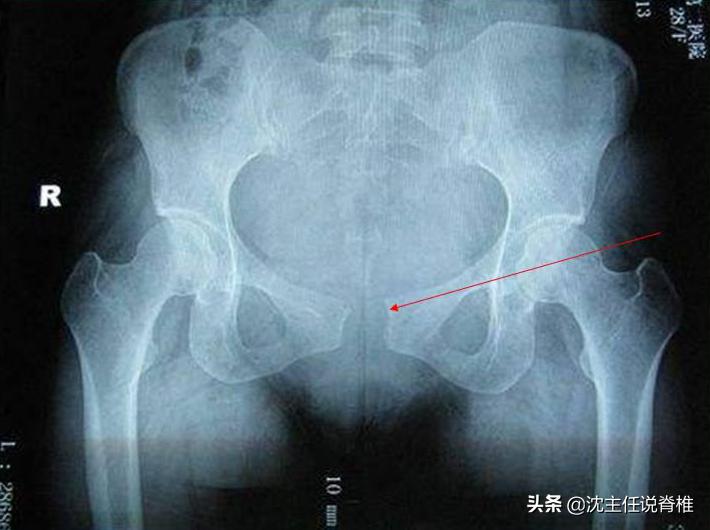

耻骨是位于骨盆前方的两片骨头,中间有空隙而非紧靠在一起。两片骨头间靠韧带及纤维软骨组织联接起来,这个区域就叫耻骨联合。一般正常人的耻骨间隙为4~6毫米,孕期内分泌改变可增宽2~3毫米,当耻骨联合分开大于10毫米时,称耻骨联合分离。